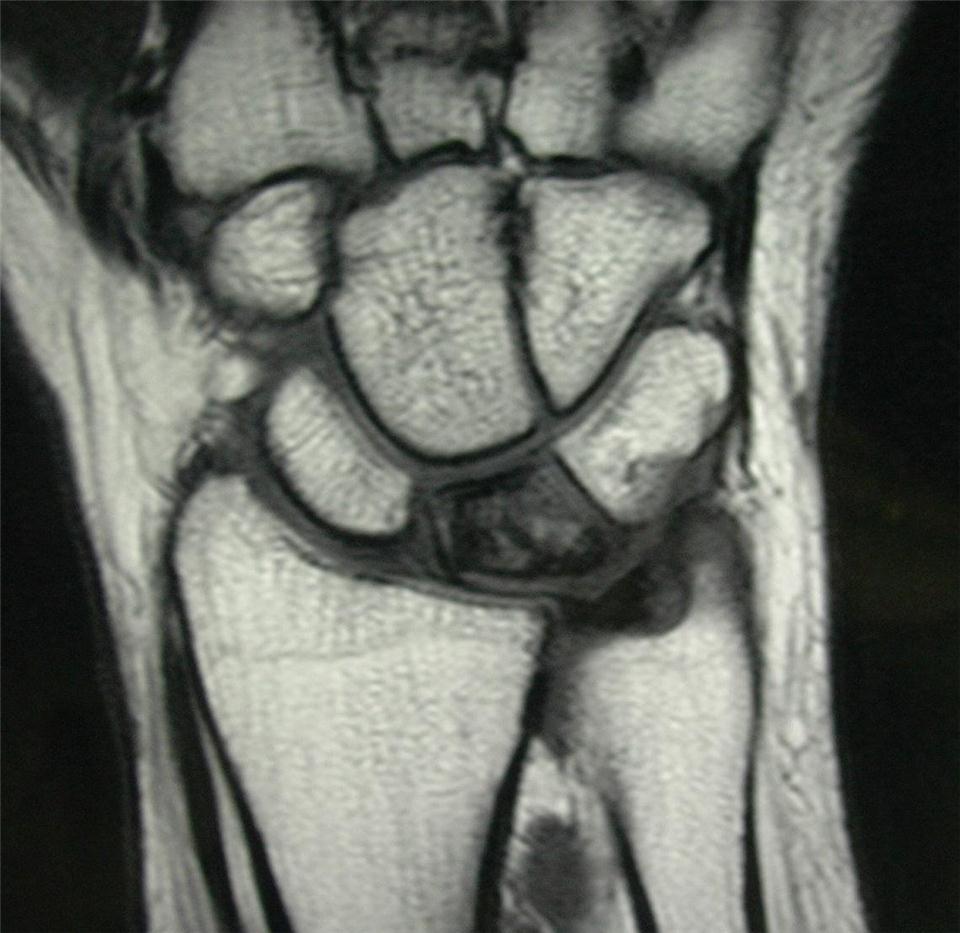

Để đưa ra chẩn đoán bệnh lý này, bác sĩ cần kiểm tra tiền sử bệnh, thăm khám sức khỏe và chụp X-quang. Trong giai đoạn đầu, kết quả chụp X-quang có thể vẫn bình thường và cần làm thêm các xét nghiệm cần thiết khác để đưa ra chẩn đoán. Phương pháp đáng tin cậy để đánh giá tình trạng cung cấp máu đến xương nguyệt ở cổ tay là chụp cộng hưởng từ (MRI). Chụp CT hay xạ hình xương cũng có khi được sử dụng.